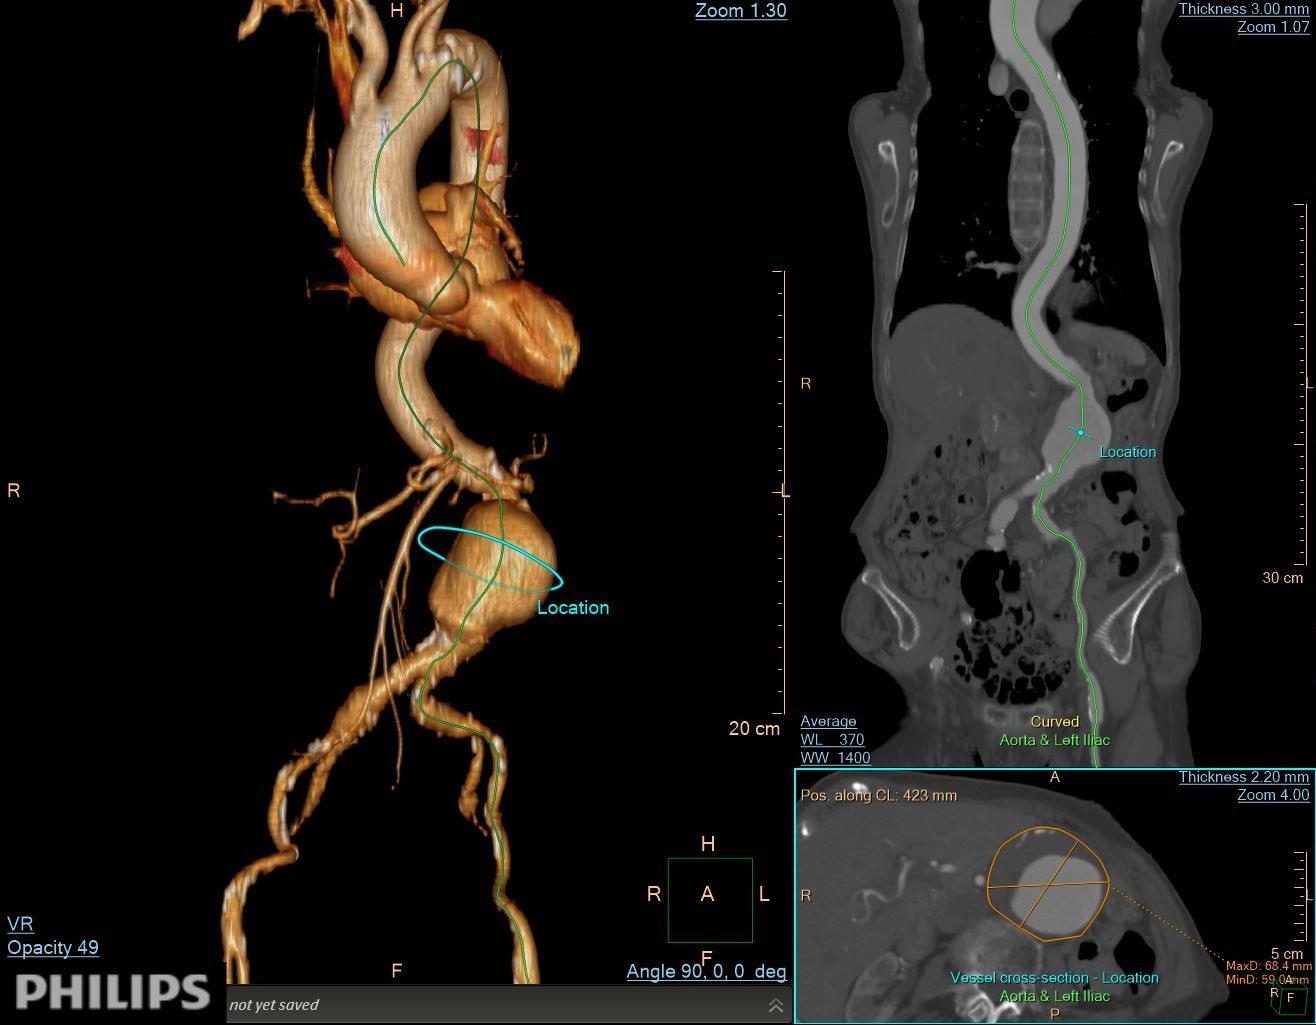

CTA demonstrated a fusiform infrarenal AAA measuring 65–68 mm with partial mural thrombus but a thrombus-free proximal neck. The neck measured 19 mm in length, tapering from 19 to 17 mm with mild (≈46¡Æ) angulation and partial mural calcification. Diffuse aorto-iliac calcification was noted with >70% stenosis and tortuosity of the left common iliac artery, while the right iliac axis appeared relatively straight. RCFA and LCFA diameters were 9.4 mm and 7.6 mm.

Under general anesthesia, bilateral common femoral arteries were accessed percutaneously under ultrasound guidance, and the pre-close technique with Perclose ProGlide (Abbott Vascular, USA) was applied. Angiography confirmed a large infrarenal AAA and left common iliac artery with severe stenosis (>70%) and marked tortuosity, while the right iliac was relatively straight. Guidewire advancement through the left side was difficult due to narrowing and vessel curvature.